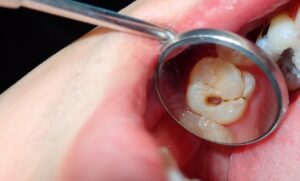

「黒い点=虫歯?」その見分け方とは?

「歯が黒いのですが、虫歯ですか?」…このように声がかかることも多く、患者様から最も多い質問でもあります。

以下に黒い点が虫歯なのか、虫歯でないのかの特徴をまとめました。

【黒い点で虫歯の可能性が高いケース】

・黒い点が明らかに“穴”になっている

・フロスを通すと引っかかる

・歯が欠けて黒くなっている

・黒い部分が触るとザラザラしている

・冷たいものがしみる

・黒い点がだんだん大きくなっている

黒い点がお口の中にあっても特に症状がない場合は「痛くないから大丈夫」と油断されがちです。

しかし、黒く見える時点ですでに中期〜後期の虫歯であることも多いため専門家によるお口の診察が必要です。

C1は虫歯が少し進行し、歯の表面に小さな黒点や溝の変色が見られるようになります。

場合によっては表面がザラつくこともあります。

C2は黒い穴がはっきり分かるようになり、歯のくぼみや穴もわかるようになります。